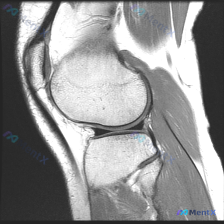

本次读片基于一张踝关节矢状位T1加权MRI图像,图像质量良好,解剖结构清晰,扫描范围涵盖胫骨远端、距骨、跟骨、舟骨及跗骨间关节。

- 整体正常表现:各骨骨髓信号均匀,无异常信号减低;骨皮质完整,无骨折线;胫距关节间隙无明显狭窄或增宽;可见范围内韧带肌腱无明确中断,软组织层次清晰,无异常肿块。

- 关键异常:距骨穹窿关节面可见明确塌陷、信号不均,局灶性低信号改变,关节面不平整。其余可见区域关节软骨表面基本光滑,无急性骨髓水肿征象。